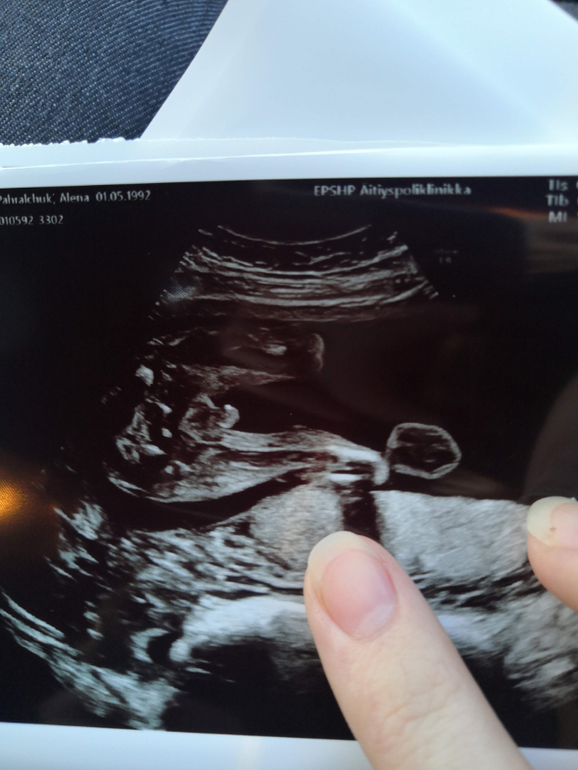

Ну и вид снизу 😆 хоть тут не прятал ничего